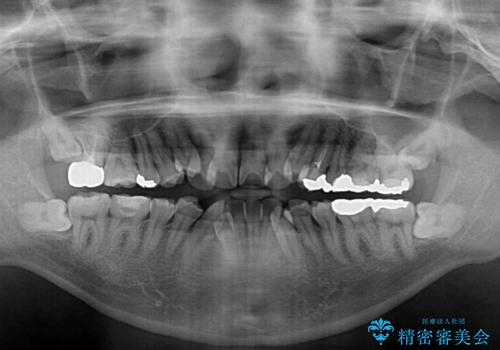

- 上下の八重歯やデコボコを気にして来院された患者様です。

上下ともに八重歯が顕著であったので、上下左右第一小臼歯4本を抜歯し、ワイヤー装置にて矯正治療を行うこととしました。

デコボコが強いことが原因で歯間部に汚れが溜まりやすい状態でしたが、矯正前にできる限り汚れが少なくなるようにブラッシングなどの指導を行い、口腔状態が改善された後にワイヤー装置を装着することとしました。